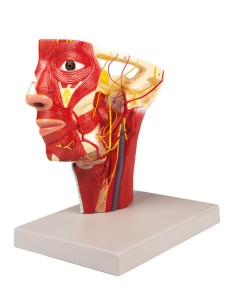

Scopri il Mondo dell’Anatomia con Modelli anatomici di Precisione

Benvenuto su Tuttoanatomia.it, il portale di riferimento in Italia per l’acquisto di modelli anatomici, poster, lettini portatili, simulatori medici e letteratura specialistica. Con i nostri modelli anatomici di 3B Scientific ed Erler Zimmer, leader mondiali nel settore, offriamo un’esperienza di apprendimento senza pari.

Modelli Anatomici Dettagliati per Ogni Necessità

Dal cranio in 22 parti con incastri magnetici ai modelli di colonna vertebrale, da quelli di articolazioni a quelli di cuore, ogni pezzo della nostra collezione è progettato per un’immersione totale nello studio dell’anatomia umana. I nostri modelli, realizzati tramite scansioni di ossa vere, garantiscono un’esperienza tattile autentica e una fedeltà di peso quasi identica agli originali.

Strumenti Didattici Innovativi per l’Educazione e la Pratica Medica

Essenziali per studenti e professionisti, i nostri modelli anatomici sono strumenti didattici che permettono di osservare le strutture anatomiche con precisione, eliminando la necessità di dissezioni o studi invasivi. Sono inoltre utili per spiegare ai pazienti le patologie, rendendo la comunicazione più efficace e risparmiando tempo prezioso.